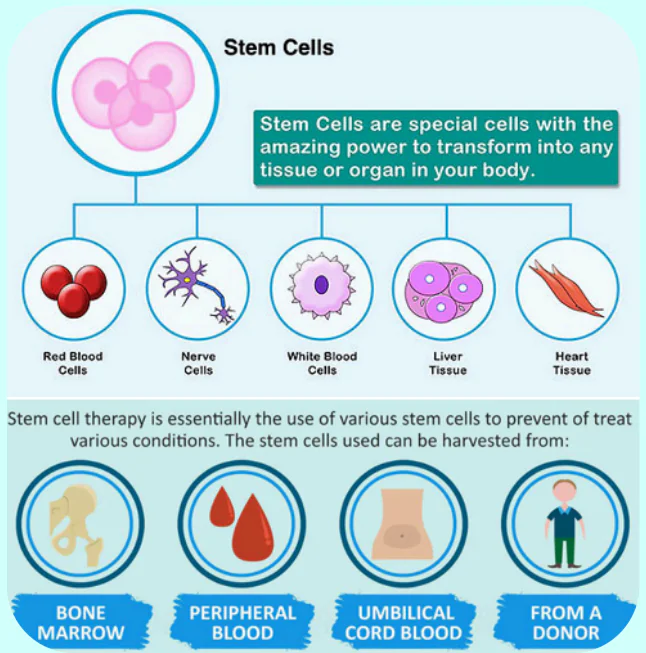

Stem cell therapy involves the use of specialized cells to repair or replace damaged tissues. This innovative approach holds potential for treating various diseases and enhancing healing processes.

What are Stem Cells?

Stem cells are special cells in our body that have the ability to repair and replace damaged tissues. They are often called the body’s “master cells” because they can develop into different types of cells such as muscle cells, nerve cells, or cartilage cells.

These cells play an important role in healing injuries and maintaining healthy organs. When the body faces damage due to disease, aging, or injury, stem cells can help support natural repair processes.